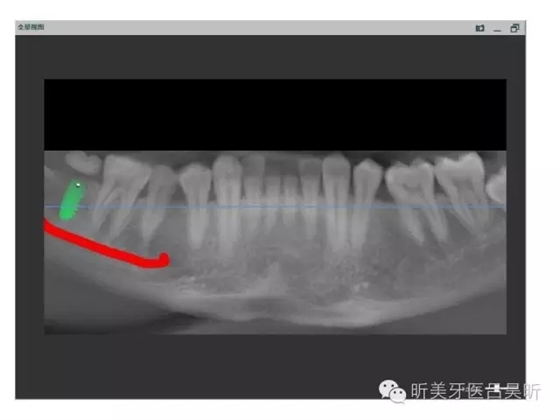

術(shù)前口內(nèi)掃描,設(shè)計冠修復(fù)方式和種植位點(diǎn)

可見種植位點(diǎn)舌側(cè)區(qū)凹陷,牙槽骨上部舌傾明顯。

擬定種植三維方向

以修復(fù)為導(dǎo)向的種植位點(diǎn)設(shè)計